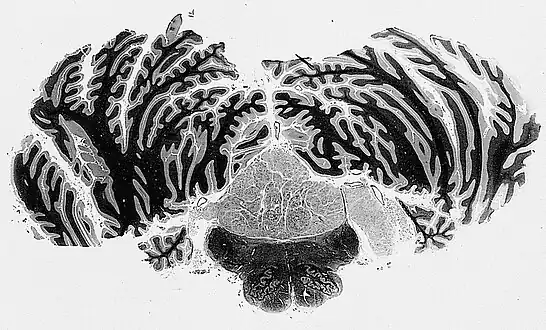

Characteristic clusters of nuclei in a dense fibrillary background suggestive of subependymoma

Subependymomas of the fourth ventricle, extending into the cerebellopontine angle via the foramen of Luschka, right side of illustration.

The diagnosis is based on tissue, e.g. a biopsy. Histologically subependymomas consistent of microcystic spaces and bland appearing cells without appreciable nuclear atypia or mitoses. The nuclei tend to form clusters.